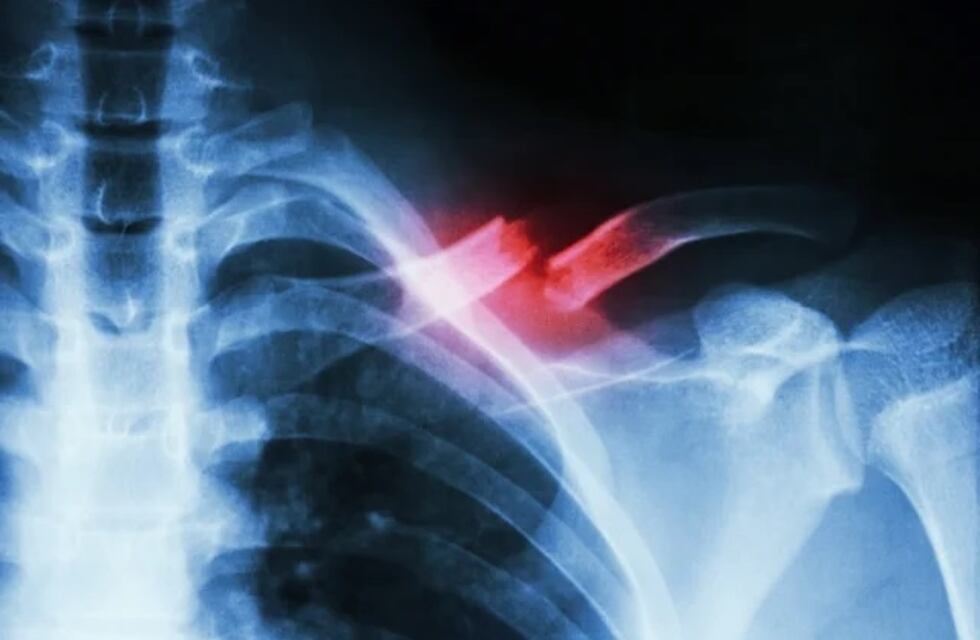

Fractura de clavícula

Es una lesión frecuente, en particular en niños y adultos jóvenes. La clavícula conecta la parte superior del esternón con el omóplato.

En el nosocomio fue recibida e ingresada a quirófano por presentar traumatismo encéfalo craneal con hematoma sud oral, fractura de clavícula izquierda, y contusión pulmonar.